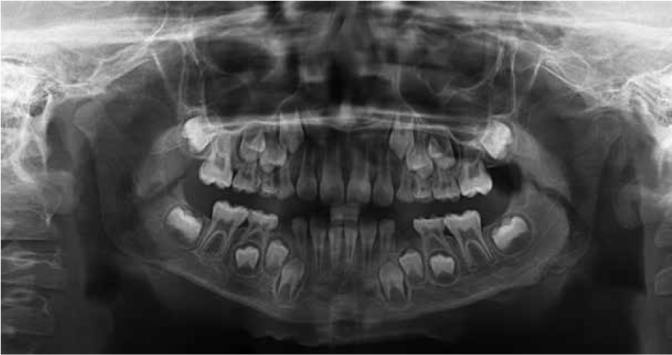

An 8-years-old boy reported to the Department of Oral and Maxillofacial Surgery, Ondokuz Mayis University with a chief complaint of hard swelling in the left posterior region of the mandible. The patient was physically healthy and any systemic condition was not detected during anamnesis. The swelling was not associated with any pain, discharge, fever, paresthesia, or difficulty in mastication. The patient did not recall or confirm any history of trauma or infection in that region. On clinical examination, a solitary, non-pulsatile and approximately 1.5 cm in diameter, bony mass was palpated at the left angle region of the mandible. The tumor found fixed to the underlying bone and the skin overlying the tumor was in a healthy appearance. The panoramic radiography and cone beam computed tomography (CBCT) scan showed a well circumscribed, radiopaque mushroom like image located on the left angle of the mandible (Figure 1, Figure 2). The 3D reconstruction of the computed tomography image revealed a pedunculated homogeneous bony mass attached to the left angle of the mandible (Figure 3). The lesion was completely excised using an extra oral approach under general anesthesia (Figure 4). The surgical specimen was submitted for histopathological examination. Histopathological examination revealed a sclerotic lamellar bone nodule with almost no intertrabecular space (Figure 5). These features confirmed the final histopathologic diagnosis to be peripheral osteoma. The post-operative course was uneventful with a satisfactory healing (Figure 6) . The patient is still under follow-up.